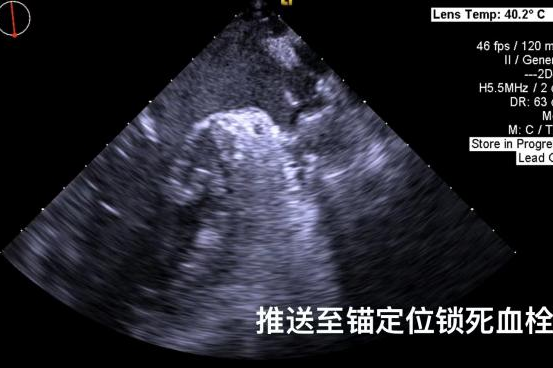

▲半展开固定伞,推送至锚定位锁死血栓

其中首场公开演示的左心耳血栓封堵病例具有极高难度,患者术前TEE显示左心耳血栓形成伴机化,血栓位于心耳中段,近中端絮状物明显。封堵机会只有一次,选型和操作稍有失误,都会增加手术风险。因此手术采取全麻,并安装了抗栓塞脑动脉保护装置,以减少术中风险。通过TEE引导下测量左心耳大小以及确认左心耳血栓位置,李岳春教授凭借自身丰富经验最终决定使用LAmbre 2632型号,采用推送式植入法将左心耳血栓牢牢锁死于远端,并且封堵器一次成型,封堵效果极佳,结束后取出脑保护装置,均未见血栓,顺利完成了此台高难度的手术,获得了学员们的一致认可。